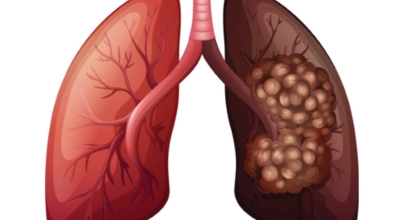

3. 폐렴 증상 - 호흡 곤란

초기에 가벼운 기침으로 시작해 호흡하는 것조차 힘들어지게 되는데요 폐에 발생한 염증으로 인해서 폐의 신전성이 감소하고, 폐를 구성하는 폐포 세포가 망가져 적정 수준의 산소를 보관하지 못하기 때문에 호흡곤란이 유발될 수 있어요.

5. 폐렴 증상 - 가슴 통증

폐렴 증상으로 가슴에 통증이 생긴다고 합니다. 폐렴의 환자들 약 90%이상은 가슴통증을 느낀다고 하지만, 숨을 쉬거나 기침을 하다 보면 가슴통증이 생긴다고 합니다. 이런 가슴 통증 폐렴 증상은 사람마다 다르다고 하는데 누구는 폐를 뾰족한 걸로 찌르는 느낌을 받는 느낌을 받는다고 하고 혹은 누군가가 폐를 잡는듯한 고통을 느낀다고 합니다. 이런 폐렴 증상이 나타나게 되면 검사를 받아보시길 바래요.